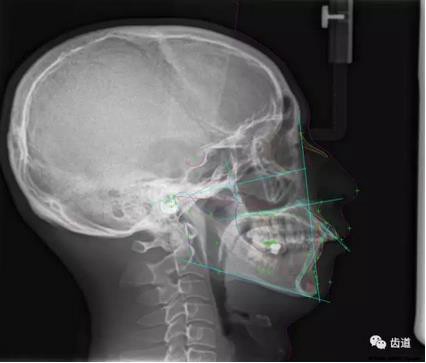

五)口腔正畸

CBCT在頜骨正畸科方面的應(yīng)用:軟件功能的強大,提供有效的數(shù)據(jù),為頜骨正畸提供了極大的幫助,免除了很多臨床醫(yī)生的手工繪圖,并有利于科研、教學(xué)等方面發(fā)展研究。

投影測量側(cè)位片影像

軟件產(chǎn)生CEPH圖像注釋,不含X線射線圖像

軟件產(chǎn)生的數(shù)據(jù)庫